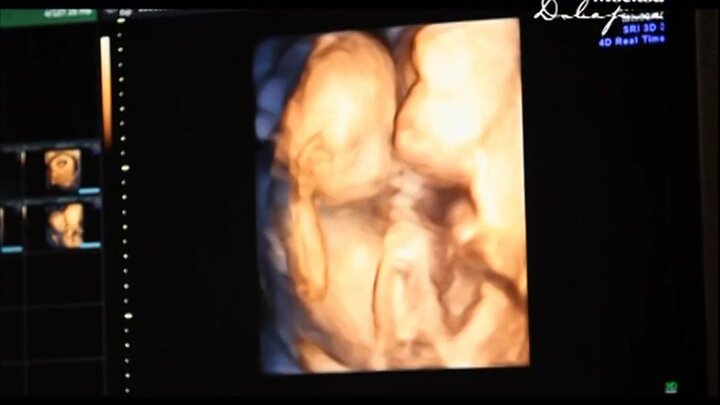

Наследство - это не только машина или квартира, но и склонность к полноте, тяга к спиртным напиткам и предрасположенность к определенным заболеваниям. Плохая генетика – тот багаж, от которого, увы, мы не можем

отказаться. Однако то, как работает механизм наследственности, по-прежнему остается загадкой. Подробности - в "Нераскрытых тайнах".